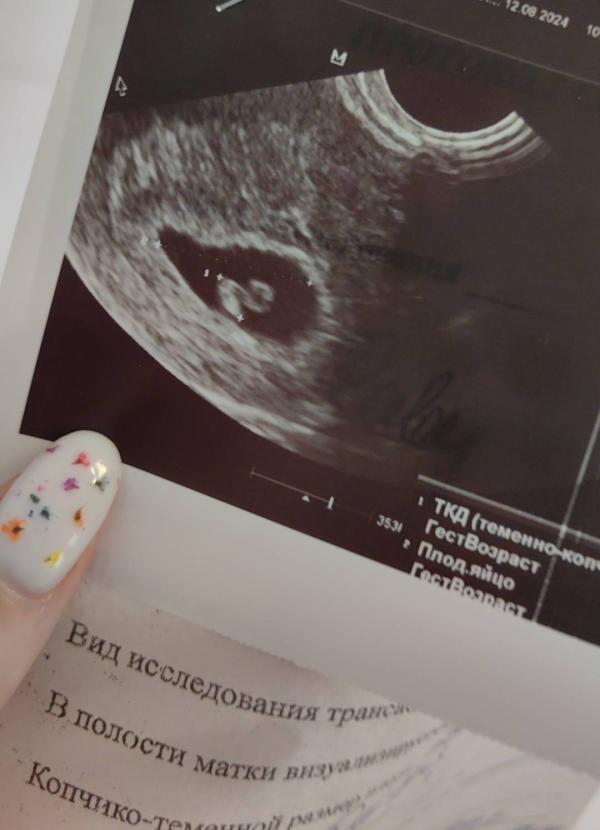

Итого мы имеем человека сроком 6,4 недели, размером 0,7 см и чсс 144 🤗